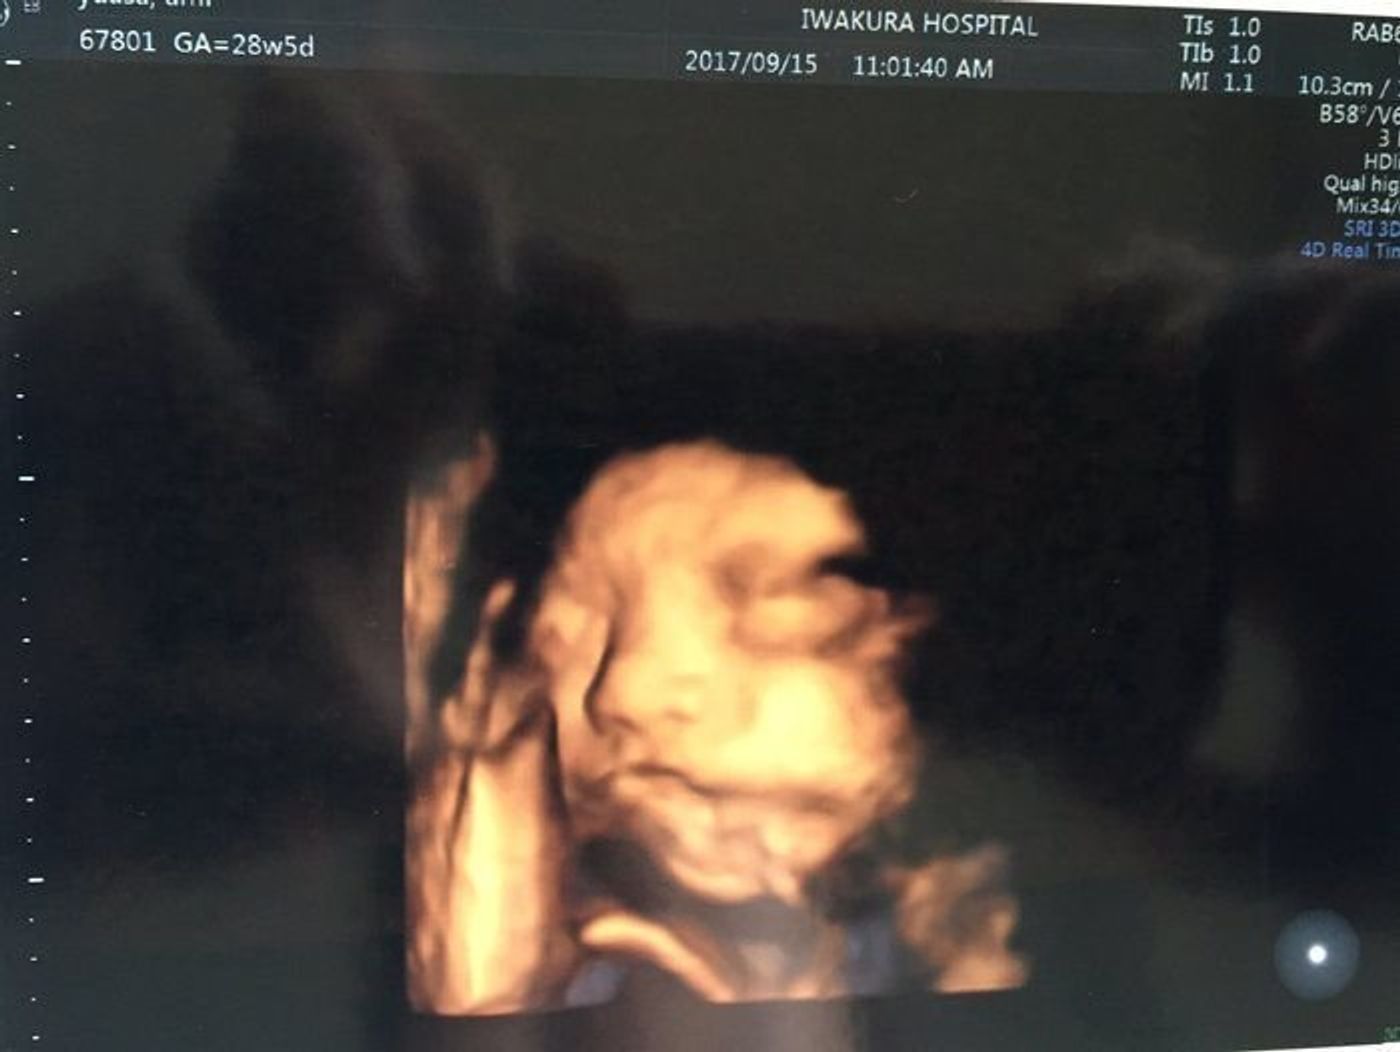

超音波エコー写真妊娠後期 (妊娠28週目~妊娠35週目) 妊娠後期 (28週目~35週目)の超音波エコー写真を紹介します。 東京都立川市 井上レディスクリニック院長。 産婦人科専門医、日本乳癌学会認定医、認定健康スポーツ医 他。 診療のかたわら、思春期から更年期の様々な女性に対しての講演活動、また、雑誌・TVなどに、出演、監修、執筆するなど多方面で今回の妊娠は切迫流産で入院などトラブル続きでしたがやっと28週目です! 何度も4Dエコーをしてもらっていますがいつもお顔を隠していたのですが今回はばっちり見せてくれました。 横顔がパパそっくりでとても可愛い~(^^) 鼻が高いのもパパに似てくれますように! 5人目にして女の子が確定しているのでお兄ちゃん達は産まれてくるのを凄く楽しみにしてます♪ 確か29週ぐらいだったと思います。 エコーに映る我が子を見てショックを受けました。 たばかりの赤ちゃんは顔も小さめで、鼻や口などのパーツが大きめには見えますが、エコー の方が鼻も口も、実物よりも大きく写っているように見えますよね。 さらに言えば、3Dエコーよりも4Dエコー

妊婦生活レポ22 エコー画像まとめ 3dエコーと4dエコー動画 妊娠28週 ちびお日記

胎児 4dエコー 8ヶ月 28週 の赤ちゃん 男の子 Youtube